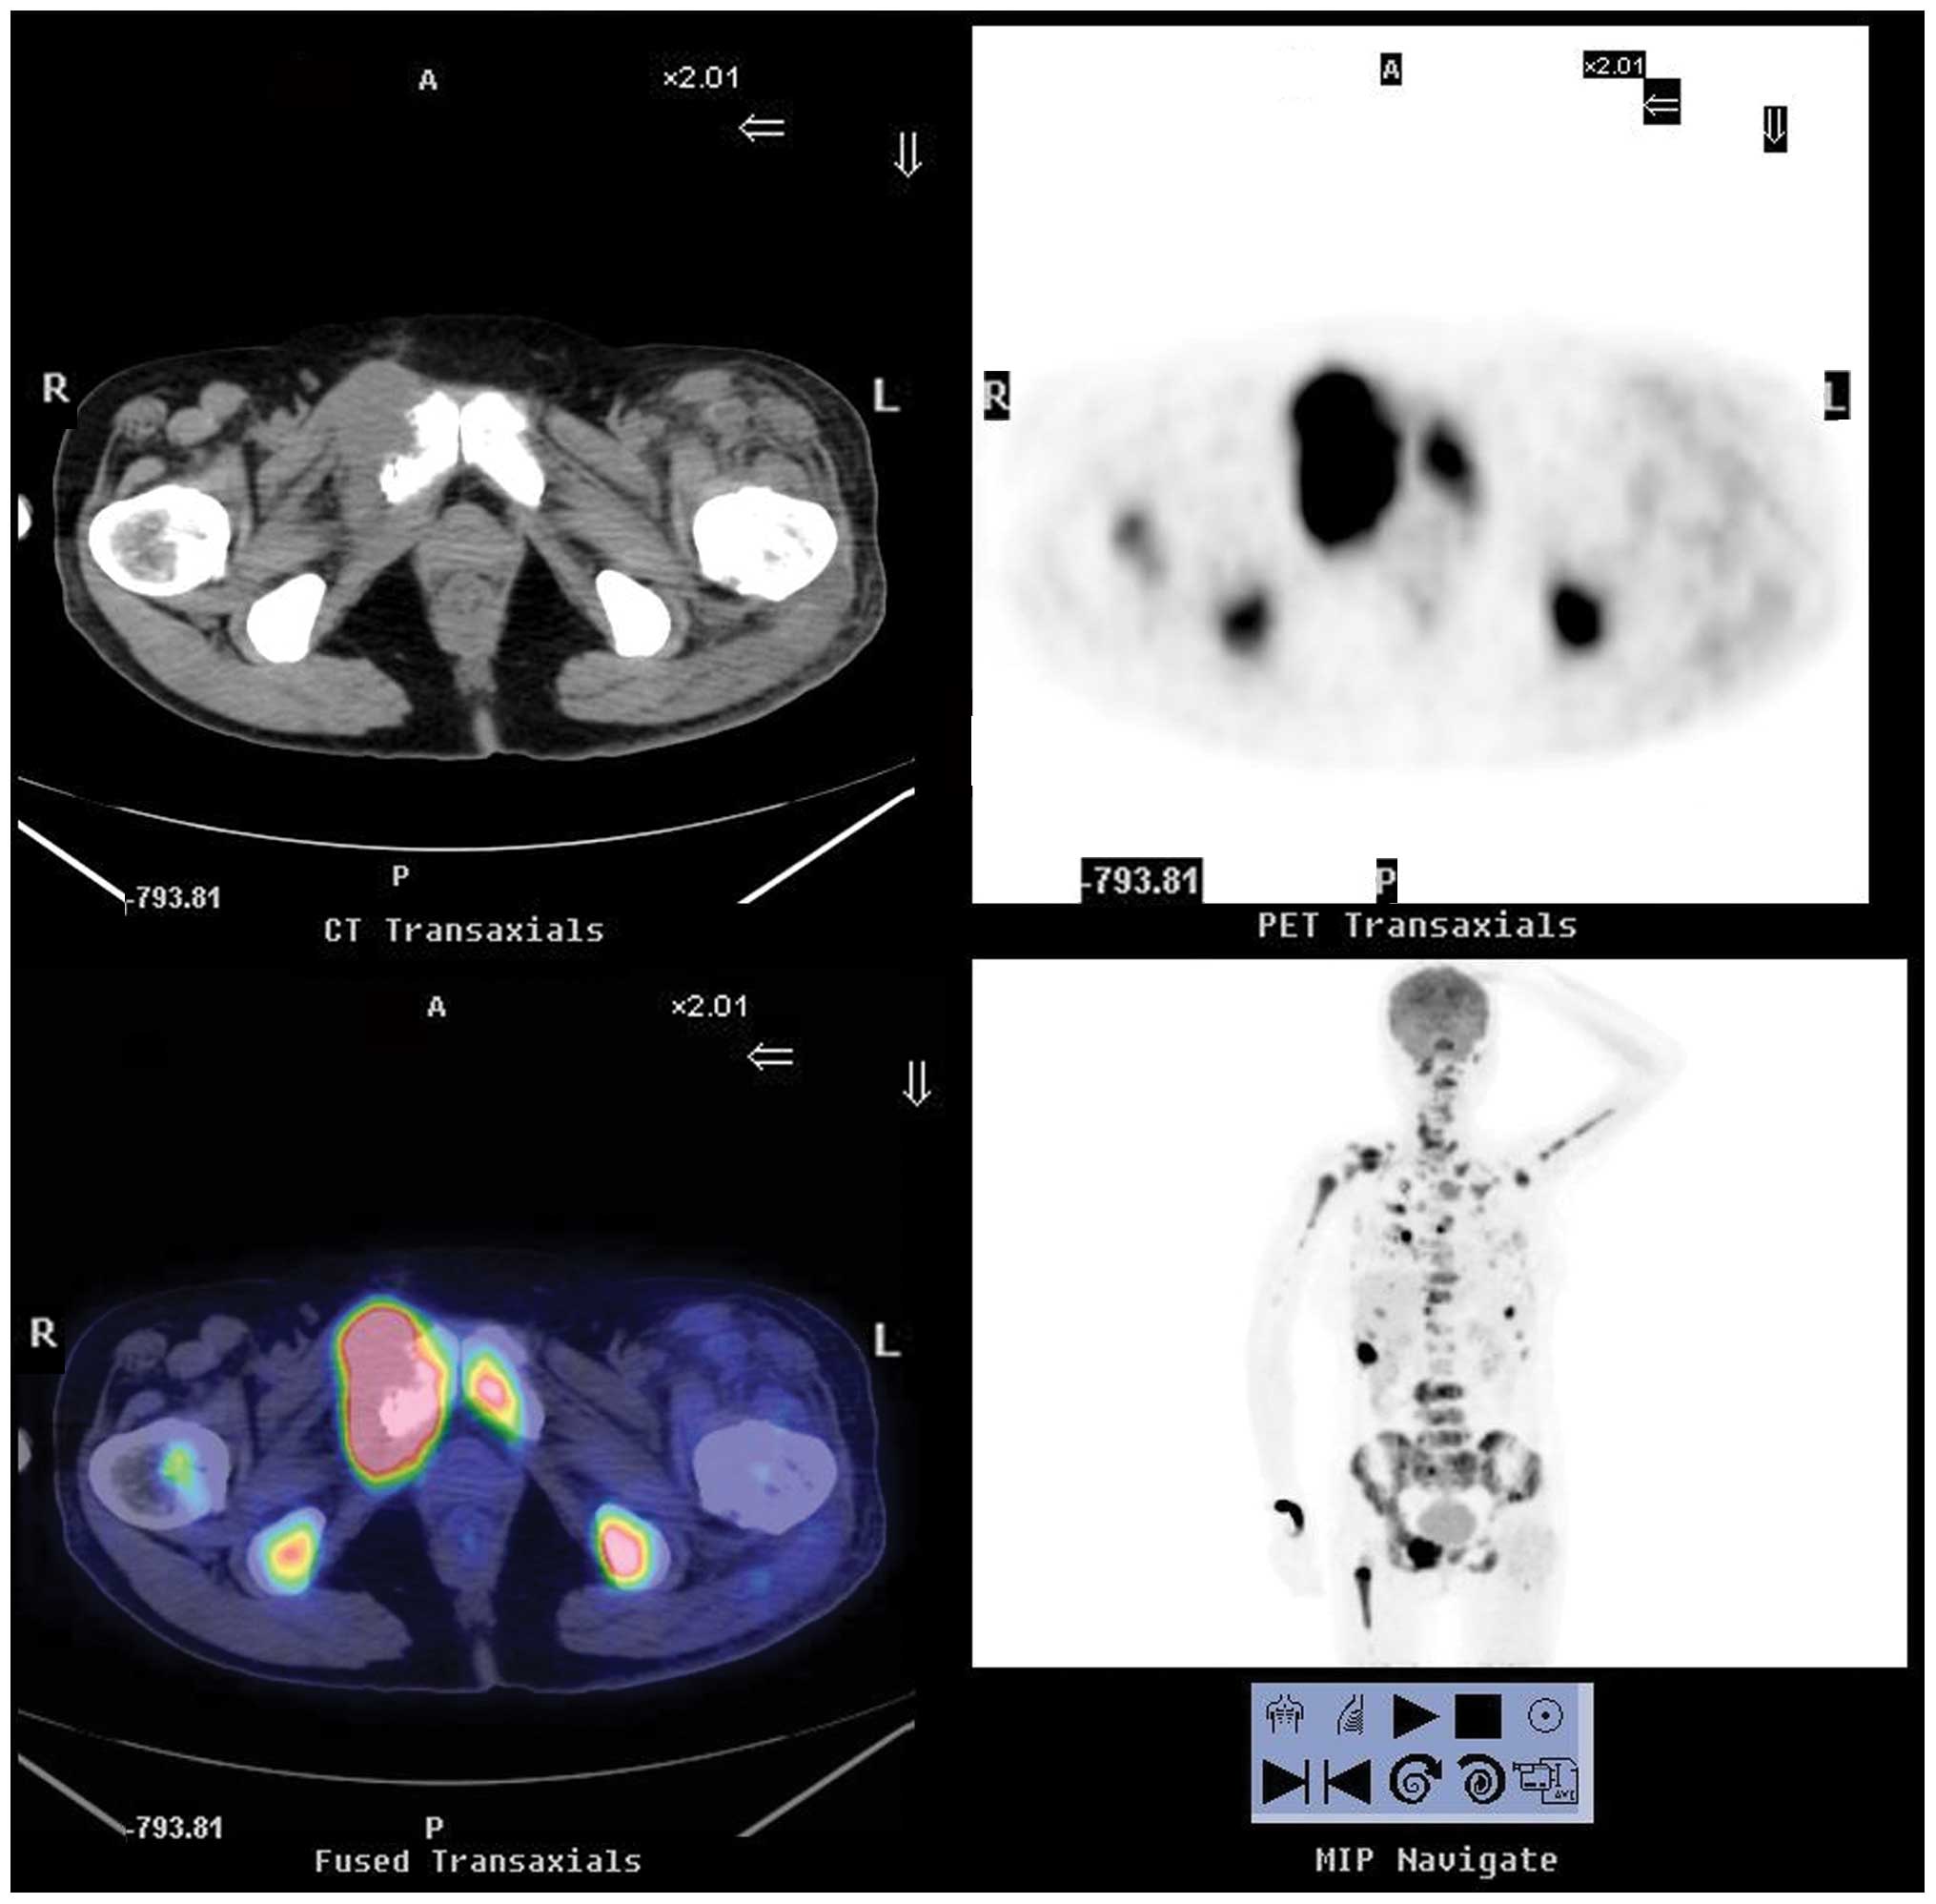

In September 2011, a 53-year-old female patient, who had no significant medical history, presented with osteodynia in the lumbar region and pelvic area that lasted several months. The 18F-fluorodeoxyglucose positron emission tomography/computed tomography (18F-FDG PET/CT) scintigraphy showed that there was extensive bone destruction with hypermetabolic osteolysis in the skull, spine, sternum, certain ribs, bilateral scapulas, ilia, pubis, ischia and left femur, which had increased 18F-FDG uptake (Fig. 1). The PET scintigraphy showed that the right lobe of the thyroid had patchy increased 18F-FDG uptake, which was highly suspicious of malignancy. The patient underwent pubic bone lesion resection 10 days later. The histological examination confirmed the diagnosis of a metastatic tumor (Fig. 2).

Figure 1.

18F-FDG PET/CT scintigraphy from September 2011, showing extensive bone destruction with hypermetabolic osteolysis in the skull, spine, sternum, certain ribs, bilateral scapulas, ilia, pubis, ischia and left femur, which had increased 18F-FDG uptake. 18F-FDG PET/CT, 18F-fluorodeoxyglucose positron emission tomography/computed tomography; A, anterior; P, posterior; R, right; L, left.